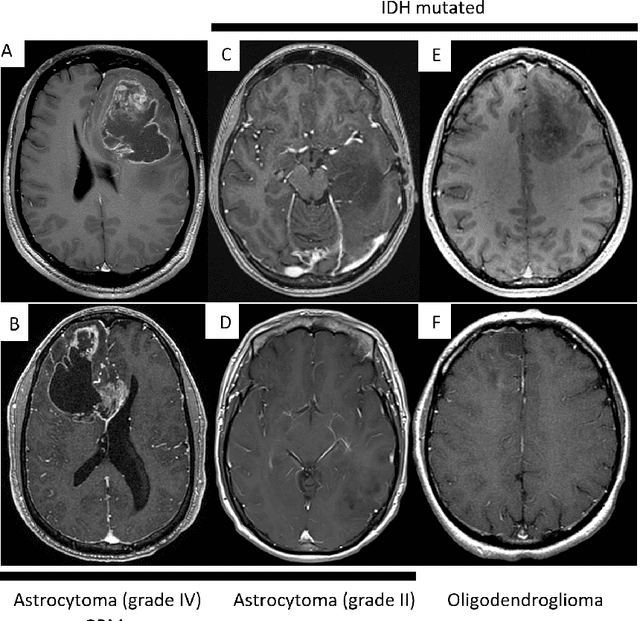

Primary brain tumors including gliomas continue to pose significant management challenges to clinicians. While the presentation, the pathology, and the clinical course of these lesions is variable, the initial investigations are usually similar. Patients who are suspected to have a brain tumor will be assessed with computed tomography (CT) and magnetic resonance imaging (MRI). The imaging findings are used by neurosurgeons to determine the feasibility of surgical resection and plan such an undertaking. Imaging studies are also an indispensable tool in tracking tumor progression or its response to treatment. As these imaging studies are non-invasive, relatively cheap and accessible to patients, there have been many efforts over the past two decades to increase the amount of clinically-relevant information that can be extracted from brain imaging. Most recently, artificial intelligence (AI) techniques have been employed to segment and characterize brain tumors, as well as to detect progression or treatment-response. However, the clinical utility of such endeavours remains limited due to challenges in data collection and annotation, model training, and in the reliability of AI-generated information. We provide a review of recent advances in addressing the above challenges. First, to overcome the challenge of data paucity, different image imputation and synthesis techniques along with annotation collection efforts are summarized. Next, various training strategies are presented to meet multiple desiderata, such as model performance, generalization ability, data privacy protection, and learning with sparse annotations. Finally, standardized performance evaluation and model interpretability methods have been reviewed. We believe that these technical approaches will facilitate the development of a fully-functional AI tool in the clinical care of patients with gliomas.